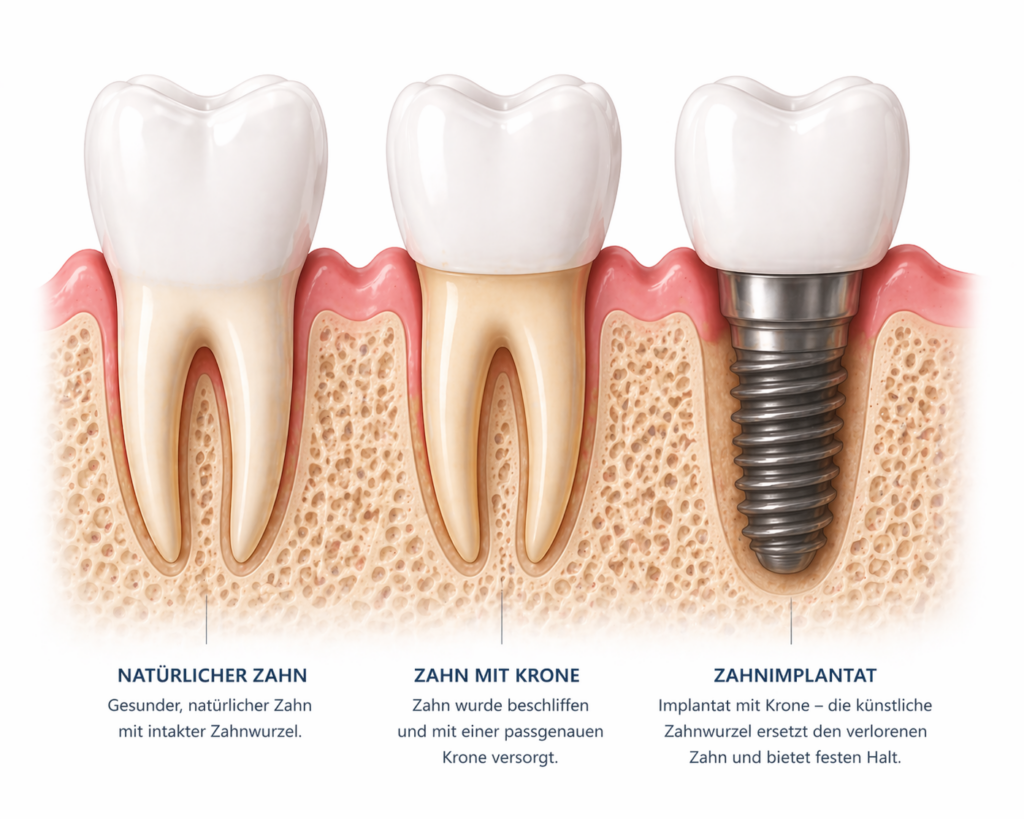

Manchmal braucht es eine neue, künstliche Zahnwurzel, die im Kiefer verankert wird – auch Implantat genannt. Auf dieser wird dann der eigentliche Zahnersatz befestigt. Diese Lösung bietet einen besonders festen Halt und kommt dem natürlichen Zahngefühl sehr nah.

Wenn nur ein einzelner Zahn ersetzt werden muss, kann eine Krone oder eine Brücke infrage kommen. Fehlen mehrere Zähne, sind oft umfangreichere Lösungen notwendig – zum Beispiel herausnehmbarer Zahnersatz oder Zahnersatz auf Implantaten. Auch ästhetische Aspekte und der gewünschte Tragekomfort spielen eine wichtige Rolle.

Auch Zahnersatz auf Implantaten ist sehr langlebig, vorausgesetzt, die Implantate sind gut eingeheilt und werden regelmäßig kontrolliert.

Wichtig ist: Eine sorgfältige Pflege und regelmäßige zahnärztliche Untersuchungen tragen entscheidend dazu bei, die Lebensdauer des Zahnersatzes zu verlängern. So lassen sich Verschleiß oder Probleme frühzeitig erkennen und beheben.